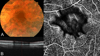

Purpose: To describe image artifacts of optical coherence tomography (OCT) angiography and their underlying causative mechanisms. To establish a common vocabulary for the artifacts observed.

Methods: The methods by which OCT angiography images are acquired, generated, and displayed are reviewed as are the mechanisms by which each or all of these methods can produce extraneous image information. A common set of terminology is proposed and used.

Results: Optical coherence tomography angiography uses motion contrast to image blood flow and thereby images the vasculature without the need for a contrast agent. Artifacts are very common and can arise from the OCT image acquisition, intrinsic characteristics of the eye, eye motion, image processing, and display strategies. Optical coherence tomography image acquisition for angiography takes more time than simple structural scans and necessitates trade-offs in flow resolution, scan quality, and speed. An important set of artifacts are projection artifacts in which images of blood vessels seem at erroneous locations. Image processing used for OCT angiography can alter vascular appearance through segmentation defects, and because of image display strategies can give false impressions of the density and location of vessels. Eye motion leads to discontinuities in displayed data. Optical coherence tomography angiography artifacts can be detected by interactive evaluation of the images.